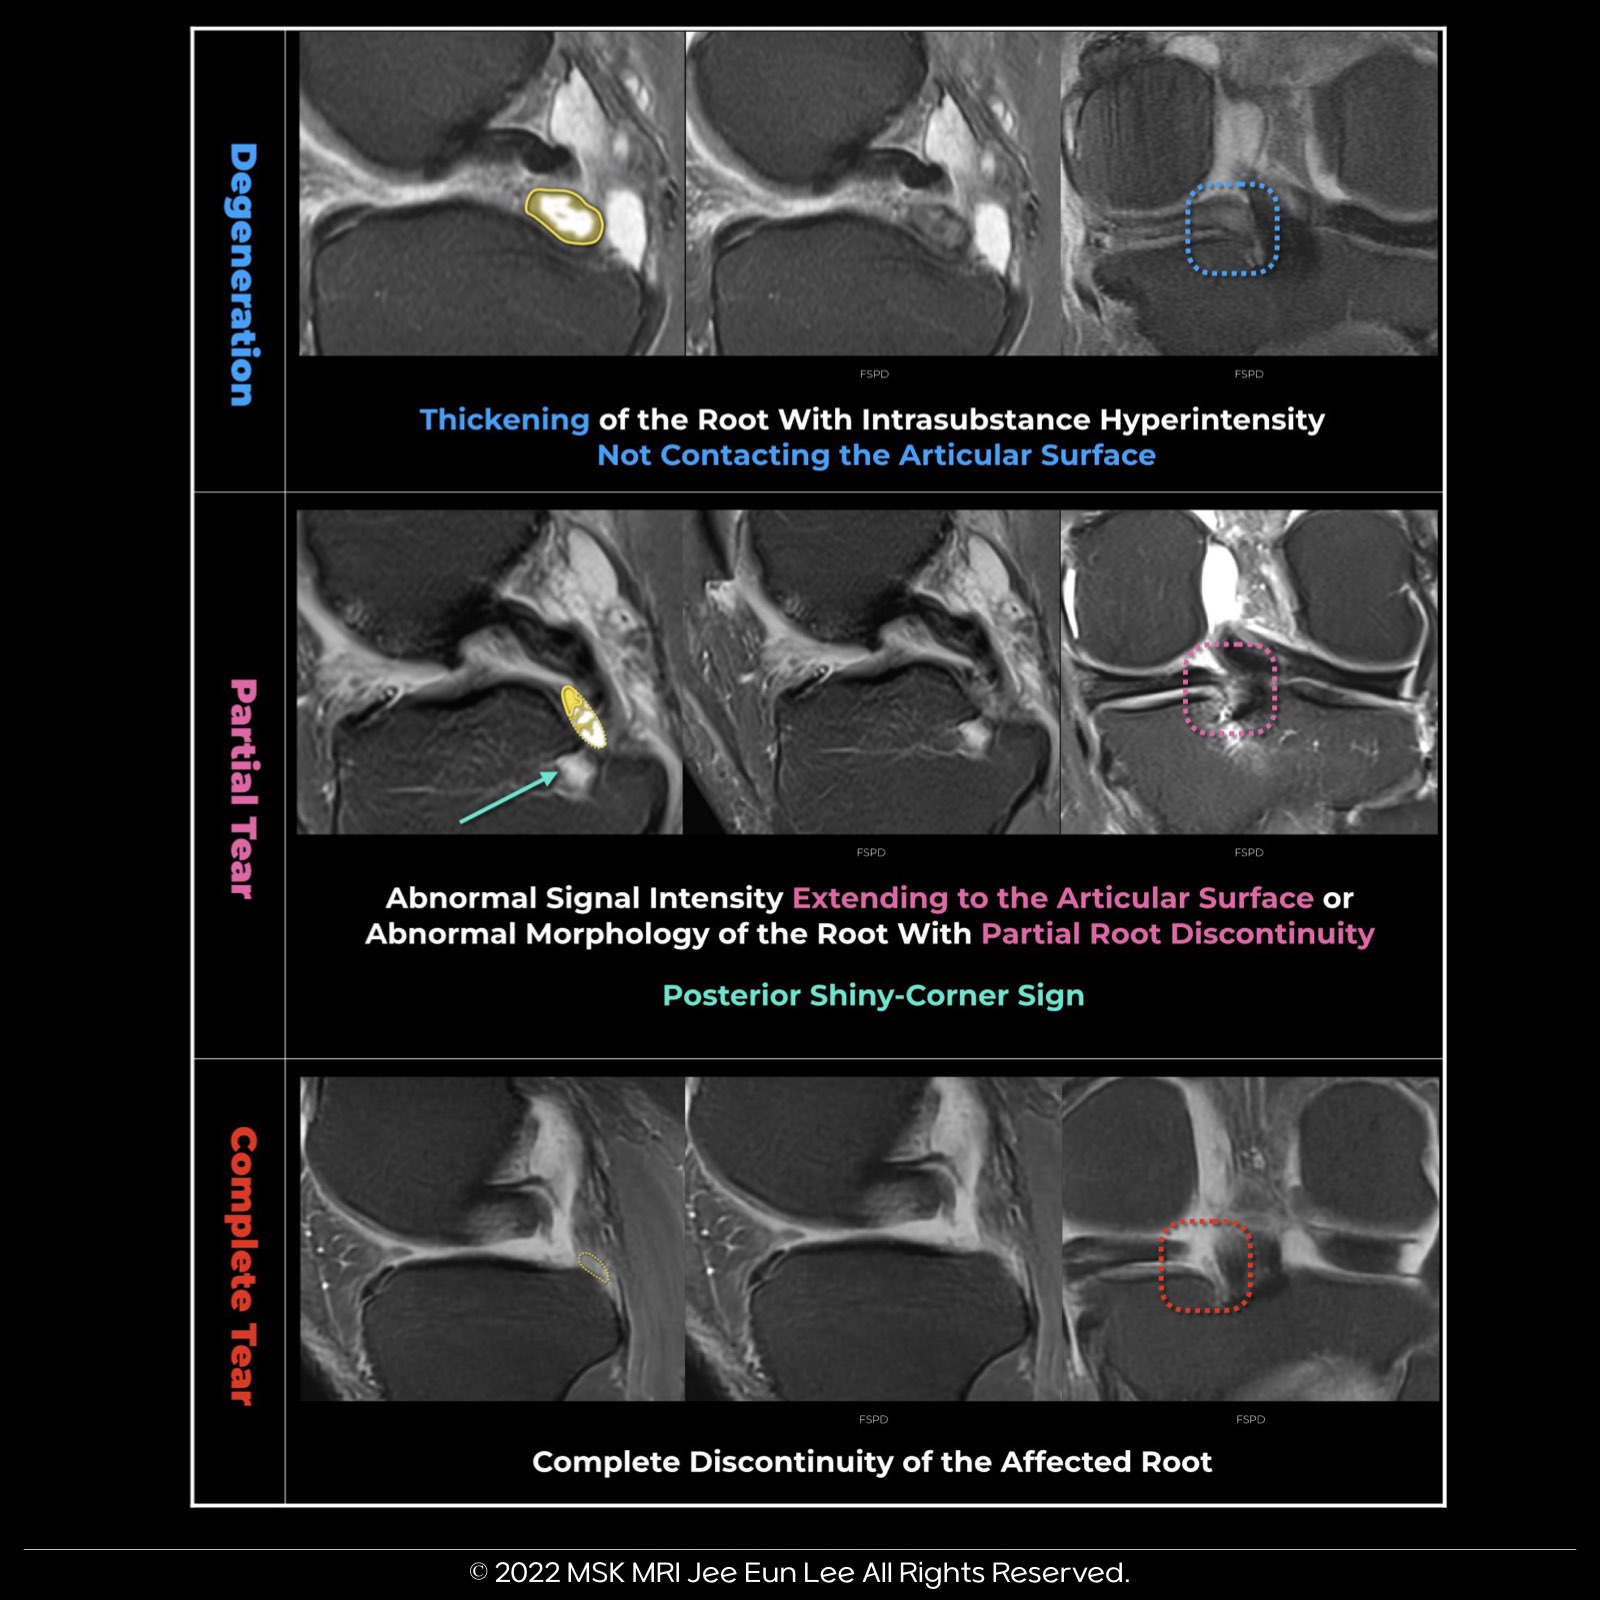

MRI Classification of Posterior Medial Meniscal Root Injuries

1. Root Degeneration:

Characterized by thickening of the root with intrasubstance hyperintensity that does not reach the articular surface.

2. Root Partial Tear:

Involves abnormal signal intensity extending to the articular surface or abnormal morphology of the root with partial discontinuity.

3. Root Complete Tear:

Indicates complete discontinuity of the affected root.